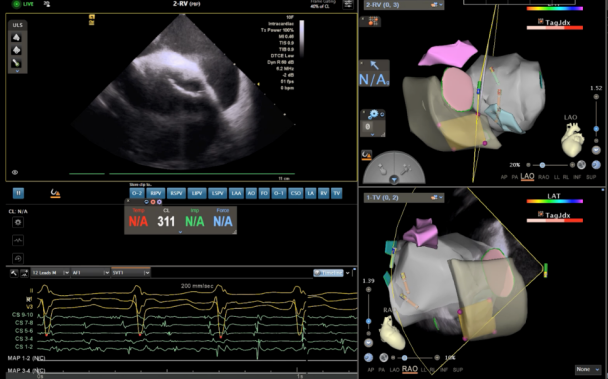

▲ICE指引下电刀辅助导丝行穿间隔穿刺,显示导丝成功进入左房。

然而,心脏反位与特殊血管入路带来的挑战并未结束——导管难以与房间隔形成有效穿刺夹角,成为阻碍手术深入的又一难题。在此关键时刻,团队在腔内超声实时引导下,采用电刀辅助穿刺技术,通过导丝成功突破房间隔组织,为进入左心房打开了关键通道。